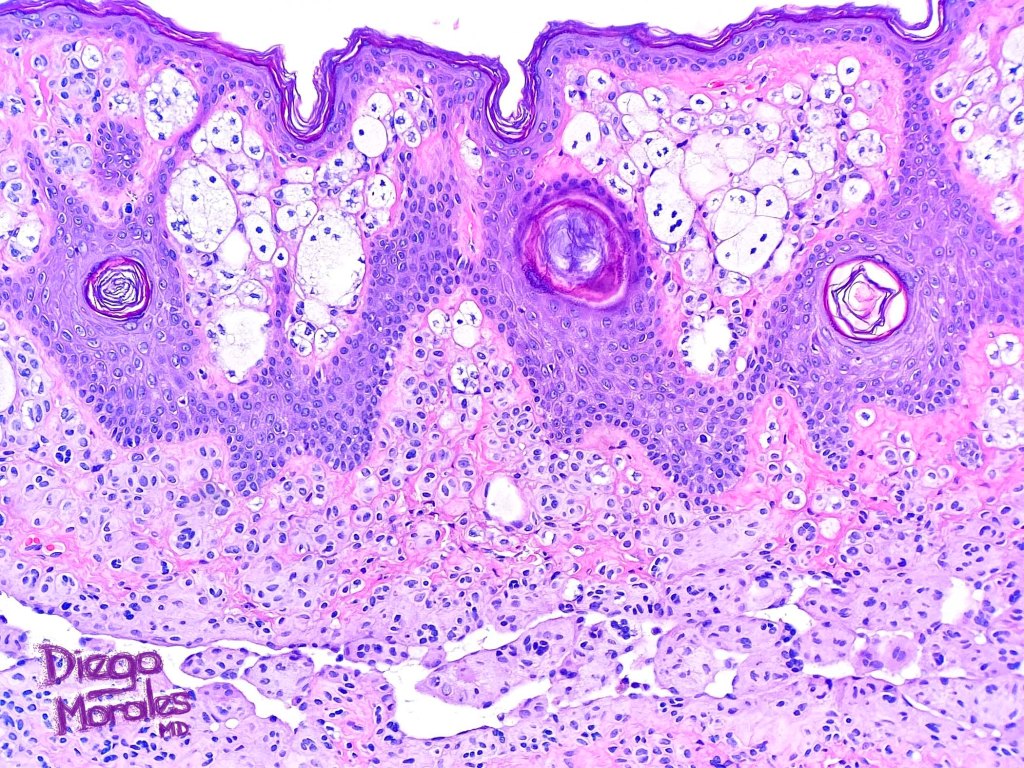

Histological features

.Balloon cell change is most often seen in banal melanocytic nevi but it has also rarely been described in cellular blue nevus, dysplastic nevus, combined nevus, halo nevus & Spitz nevus. Lesions with <50% of balloon cells are sometimes described as nevi with balloon cells. Nevi with >50% balloon cells are described as balloon cell nevus.

.Balloon cell nevs genrally has uniform, hyperchromatic nuceli (as opposed to the vesicular nuclei with prominent nucleoli) seen in melanoma. Mitoses are absent.(In my experience, balloon cell melanoma is more common than balloon cell nevus).

. In some balloon cell nevi, the microvesicles may result in nuclear scalloping reminiscent of a sebaceous tumor. In cases where there is real doubt, immunohistochemistry (S100), SOX10) will resolve the problem.

The importance of the entity is that it must always be distinguished from balloon cell melanoma. All cases should be scrutinized very carefully for pleomorphism and mitotic activiy before rendering a diagnosis of balloon cell nevus.